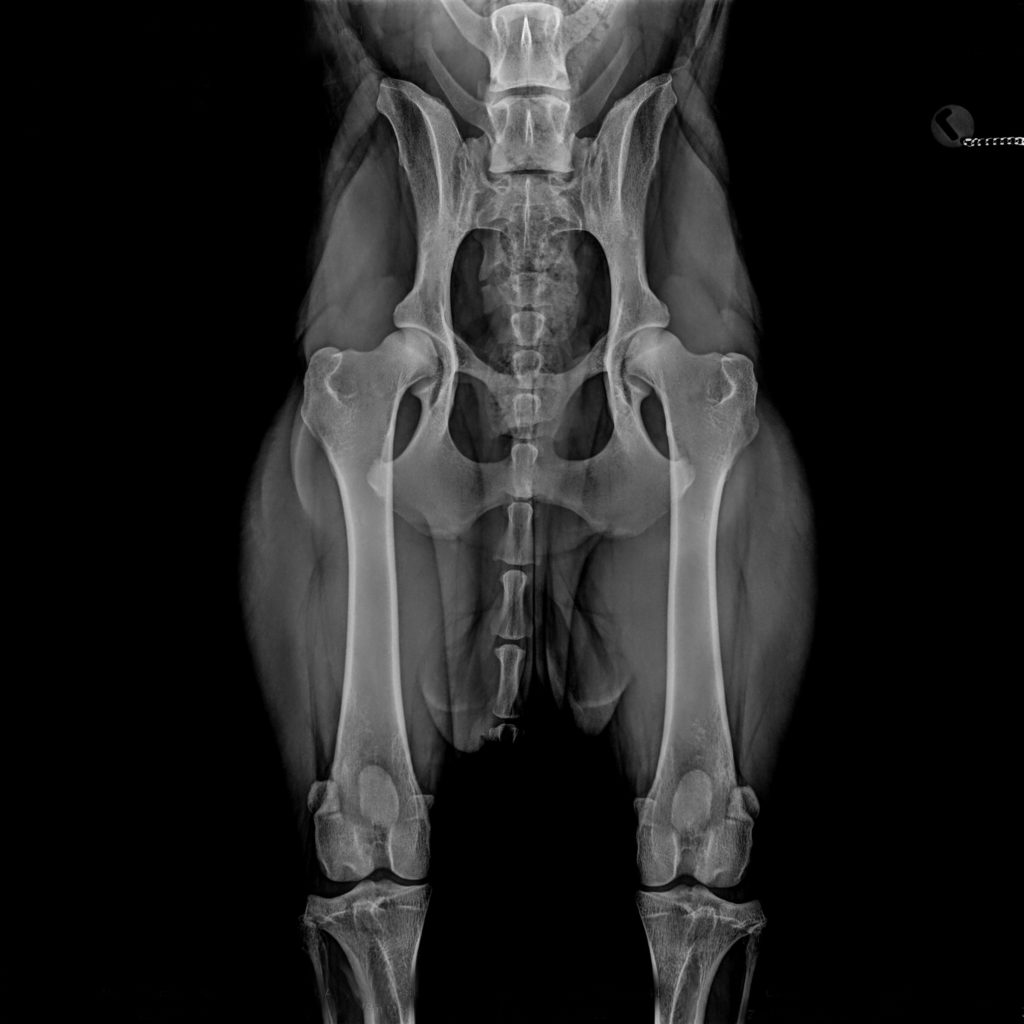

Richtlinien HD (Hüfte) Röntgenaufnahme

a. Ventrodorsale Aufnahme (Abb 4.)

1. Die Aufnahme muss in Sedation durchgeführt werden.

2. Das gesamte Becken einschließlich Kniegelenke müssen abgebildet werden.

(Abb 4.)

3. Becken muss symmetrisch abgebildet werden. Foramina obturatoria und Darmbeinschaufel beachten. In der kurzen Achse darf das Becken nicht überdreht werden. (Keine „ Katzenaugen“ der Foramina obturatoria!)

4. Oberschenkel müssen parallel zueinander und zum Tisch gelagert werden. Beide Patellae sollten in der Mitte der Trochlea femori und auf der Höhe der Fabellae sich befinden.

5. Bildqualität muss ausreichend sein, um dorsalen Pfannenrand erkennen zu können.

BorakVet Richtlinien HD (Hüfte) Röntgenaufnahme Abb4.

Abb. 4